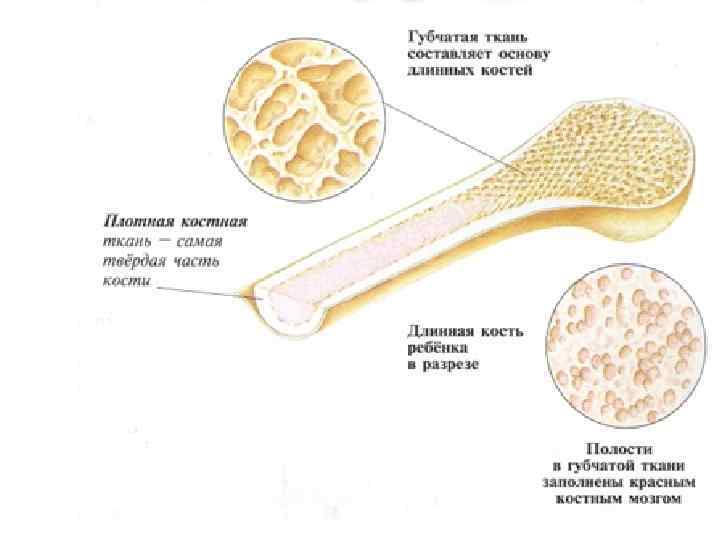

Изучение костного мозга: анатомия и функции